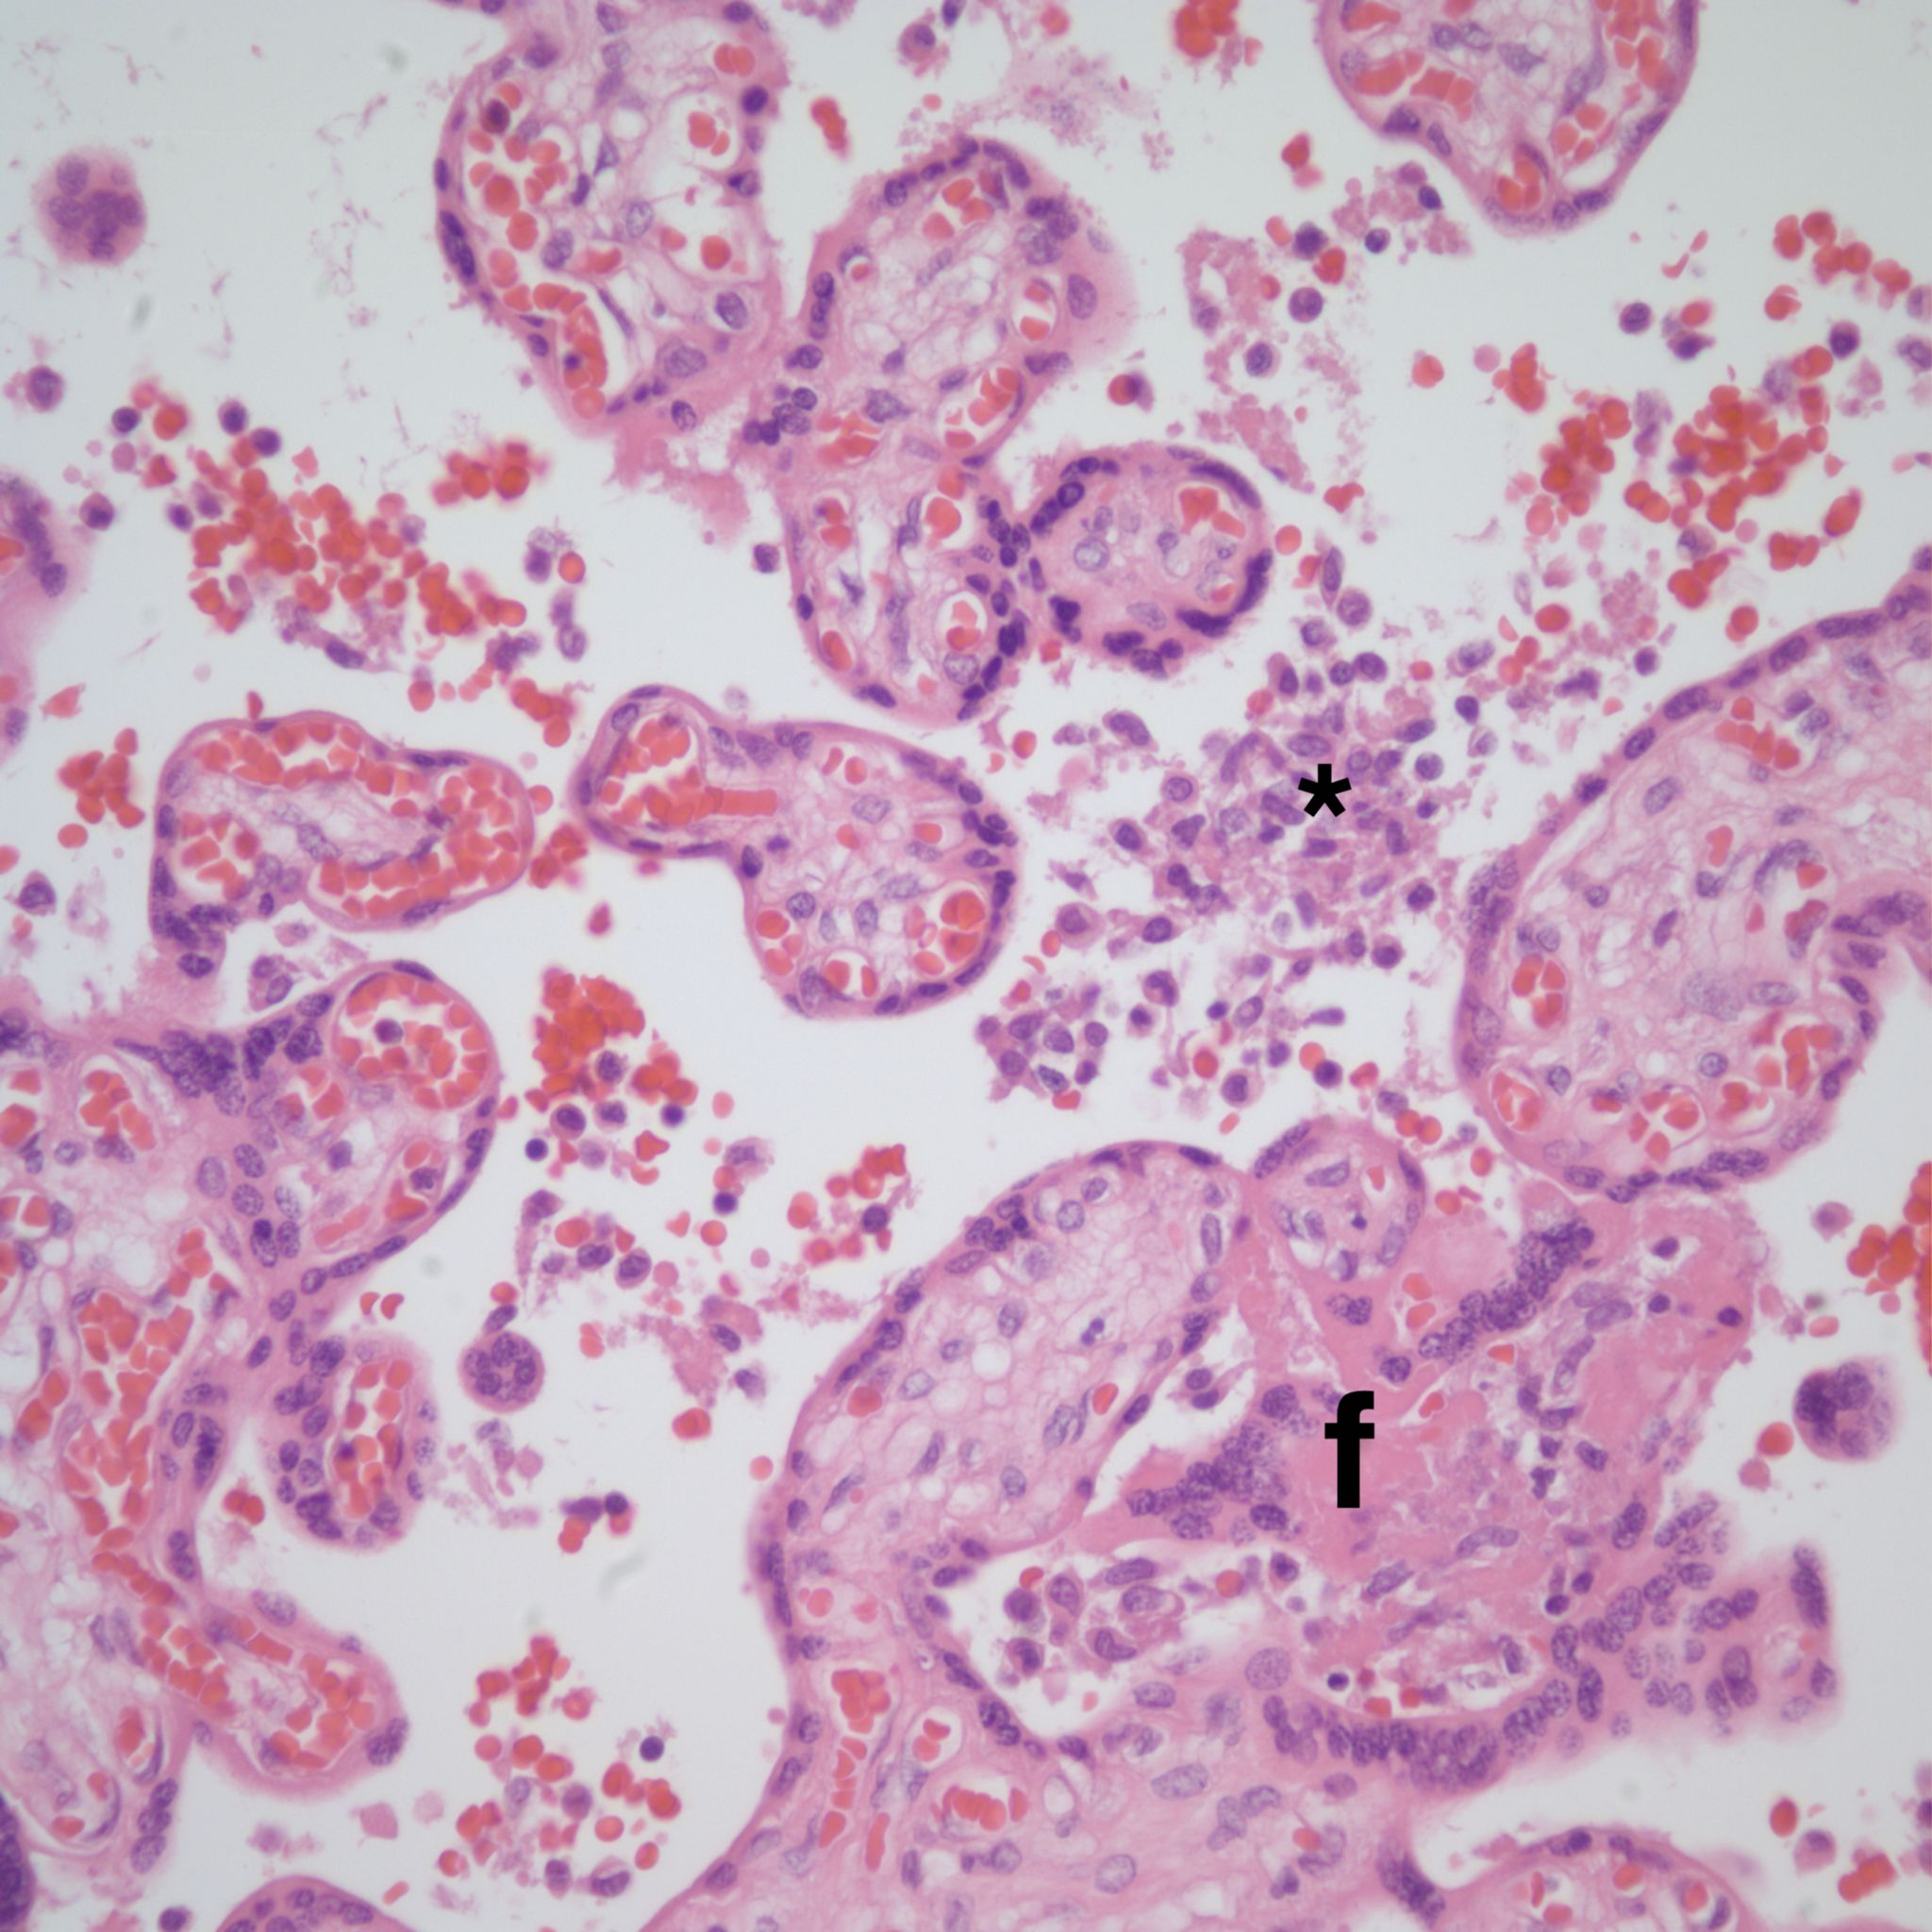

There is a focus of intervillous fibrinoid with no definite cytotrophoblast that is not re-covered with syncytium suggestive of recent syncytial injury (F). (10x, H&E)

Microscopic criteria: The primary criterion is monocytes clustered in the intervillous space which can be confirmed by CD 6810,17. The monocytes often have kidney bean shaped nuclei and prominent cytoplasm. Some other consensus criteria are that the inflammatory cells in the intervillous space should be at least 80% monocytes, and these should be maternal cells1,17.